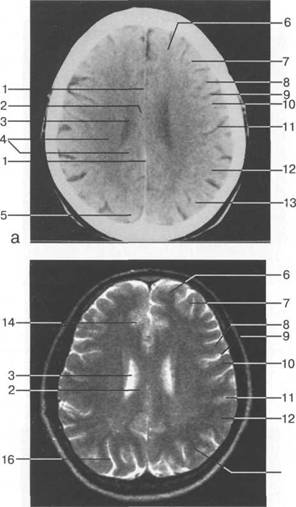

В латеральных отделах дно передней череп 13513u2010n 85;ой ямки образовано крышами глазниц, а в центральном - продырявленной пластинкой. Базальные отделы лобных долей представлены ко

ные извилины (рис. 1.10). Структуры средней череп 13513u2010n 85;ой ямки ограничены спереди малым крылом основной кости, снизу - большим крылом, сзади - передней поверхностью пирами «edge» «bone»

Содержимое средней череп 13513u2010n 85;ой ямки представлено базальными отделами височной доли.

цистерна четверохолмия; 14 -прямой синус; 15 -лобный рог; 16 - головка хвостатого ядра; 17 -перед

теменно-затылочная борозда; 11 - семиовальные